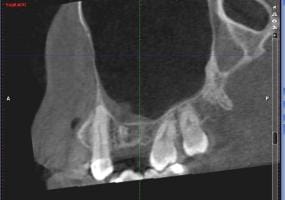

Esta semana me hicieron un tac, porque en la orto y en la radiografía periapical no salía nada. Le adjunto imágenes del mismo, y le agradecería enormemente su opinión.